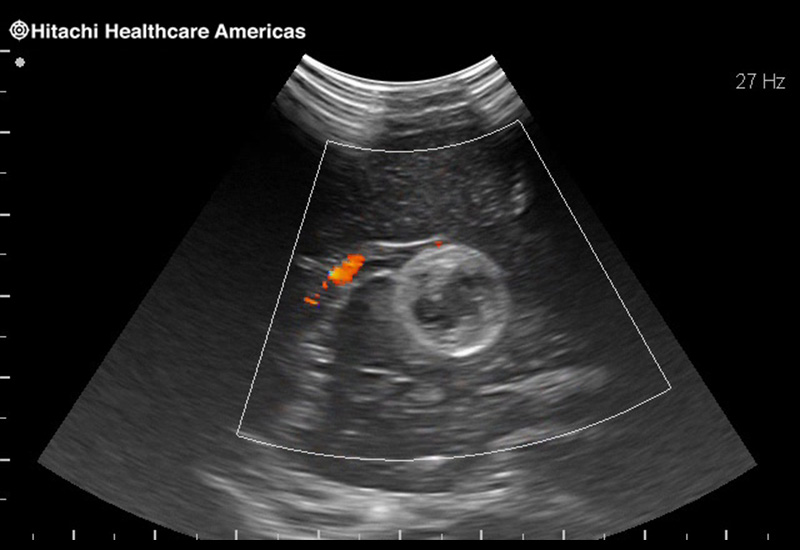

Superior guidance for all applications

Fujifilm Healthcare Americas is committed to designing tools that help surgeons navigate inside the human body and provide the necessary information to immediately make critical surgical decisions.

Fujifilm Healthcare's dedication to Surgeons provides outstanding ultrasound technology, professional support and the specialized tools necessary to best perform comprehensive real-time ultrasound imaging in Breast Surgery, General Surgery, Laparoscopic Surgery, Neurosurgery, Robotic Surgery and Surgical Oncology.

Fujifilm Healthcare’s ARIETTA Precision features state-of-the-art digital architecture and advanced imaging technologies to redefine the capabilities of surgical ultrasound.

Fujifilm Healthcare’s ARIETTA Precision features state-of-the-art digital architecture and advanced imaging technologies to redefine the capabilities of surgical ultrasound.